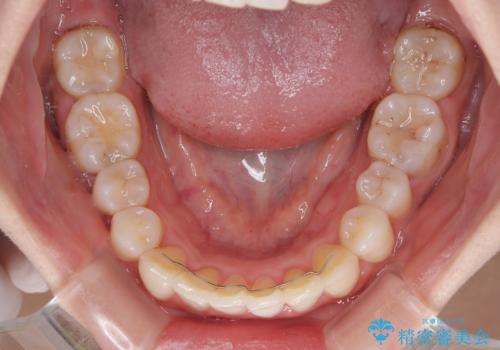

- 上下前歯のデコボコを改善したいとのことで来院された患者様です。

マウスピースを長時間装着し続ける自信はあまりないとのことでしたが、目立たない装置であれば頑張って装着するとのことで、インビザラインによる矯正治療を行うこととしました。

初めの1年くらいは何とか頑張って装着してくださいましたが、途中から変化をあまり感じられなくなり、日々の装着時間は徐々に短くなってしまいました。

前歯のデコボコはもっと改善できましたが、3年半が経過し、初診時と比べたら大幅に良くなったとのことで終了することとなりました。